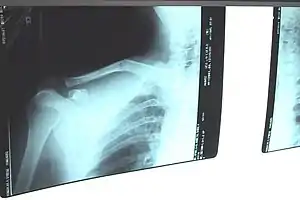

Fratura de clavícula

Uma fratura de clavícula é uma fratura óssea na clavícula.